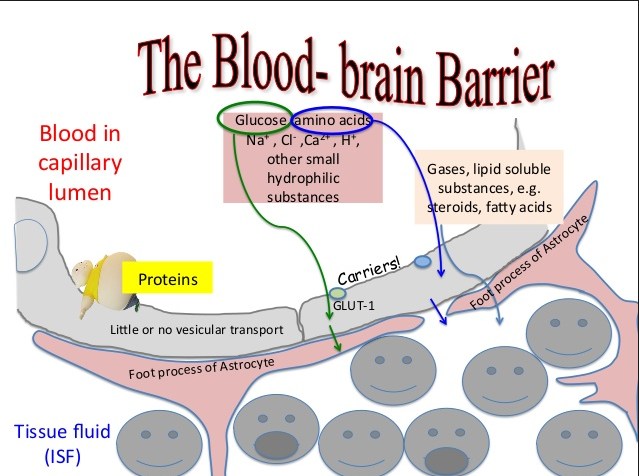

55 brain levels of thought

58 brain Septum attacks on Sept 11,2001